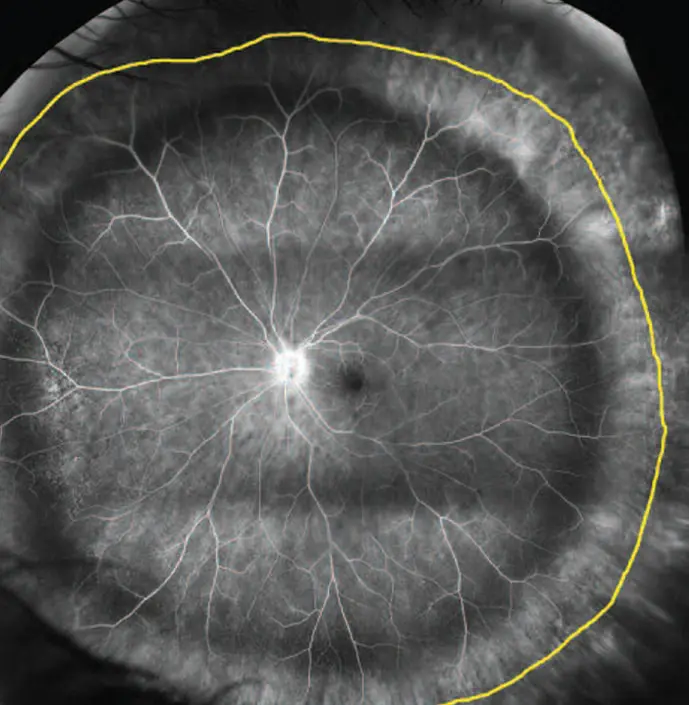

درگیری شبکیه در دیابت یا همان رتینو پاتی دیابتی مراحل و شدت مختلفی دارد. در حالت اولیه و خفیف ممکن است درمعاینه هیچگونه درگیری مشهود نباشد (هرچند امروزه با استفاده از دستگاه های تصویر برداری و آنژیوگرافی پیشرفته می توان عوارض چشمی دیابت را در مراحل ابتدايی هم تشخیص داد). تشخیص زودرس، معاینات دوره ای و پیشگیری و درمان مناسب میتواند از پیشرفت رتینوپاتی و نابینایی جلوگیری کند. در صورت عدم تشخیص و عدم پیگیری، ممکن است عوارض شدید چشمی ایجاد شود. این عوارض عبارتند از ایجاد عروق شکننده و غیر ضروری، خونریزی، جدا شدگی و در نهایت تخریب شبکیه؛ به این مرحله، رتینوپاتی پرولیفراتیو اطلاق می شود که درمان آن دشوار است.

تصاویری از عوارض چشمی دیابت